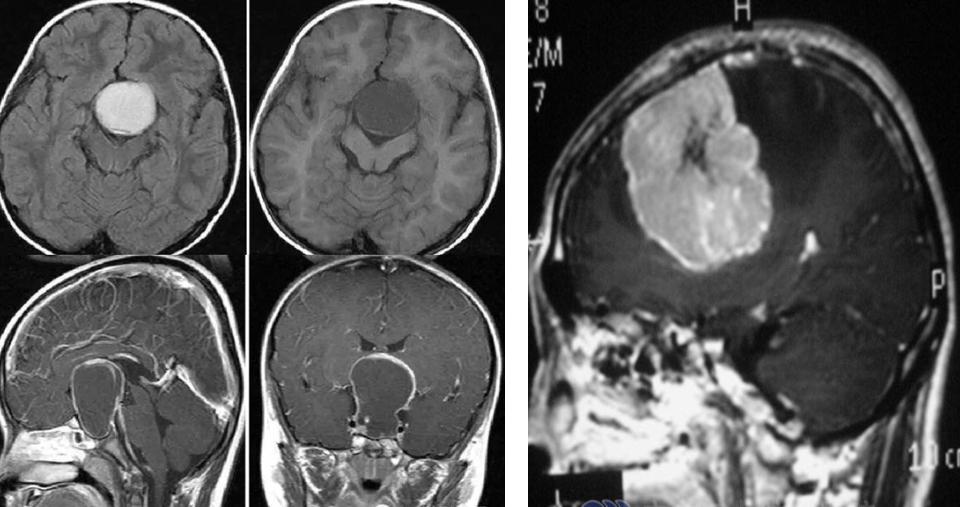

大家可以看到这张片子,大大的白颜色的就是脑内长瘤子了,脑里长的瘤子挤压了正常的空间,就像我的床只能睡一个人,我非要睡三个人,有一个人一定会挤到地下去的,那么脑内的空间也是这样,没有它的位置。

大家可以看到灰蓝色的越大,脑积水越厉害,所以孩子也会表现为呕吐。如何发现脑积水的这个情况是被占位、被颅压高导致非常容易,做一个影像学的片子,比如做一个CT、做一个磁共振,就可以看到脑子里长没长瘤子、有没有出血、有没有压力高造成脑积水,这个问题就非常容易地解决了。